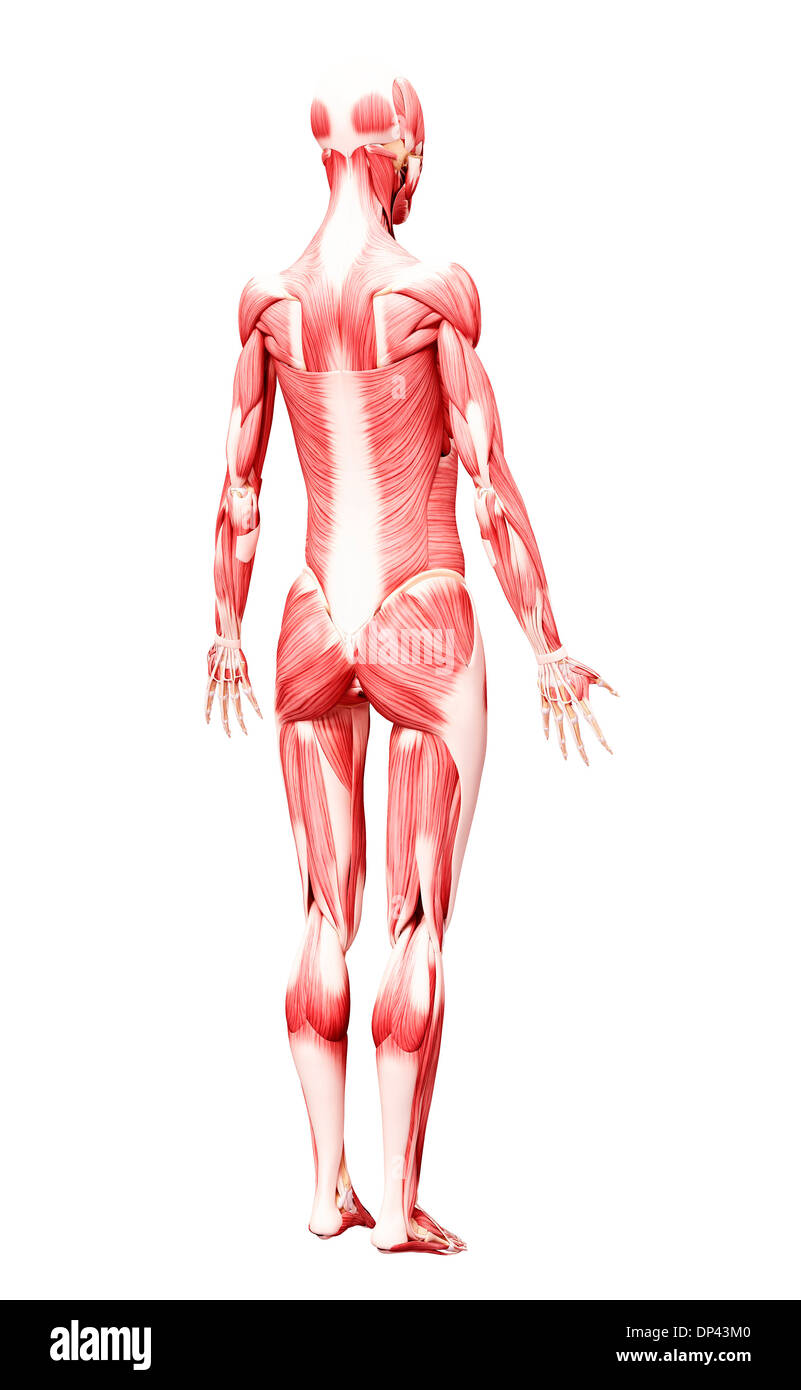

Les droits de l'Anatomy, artwork Banque D'Imageshttps://www.alamyimages.fr/image-license-details/?v=1https://www.alamyimages.fr/les-droits-de-l-anatomy-artwork-image65244256.html

Les droits de l'Anatomy, artwork Banque D'Imageshttps://www.alamyimages.fr/image-license-details/?v=1https://www.alamyimages.fr/les-droits-de-l-anatomy-artwork-image65244256.htmlRFDP43M0–Les droits de l'Anatomy, artwork